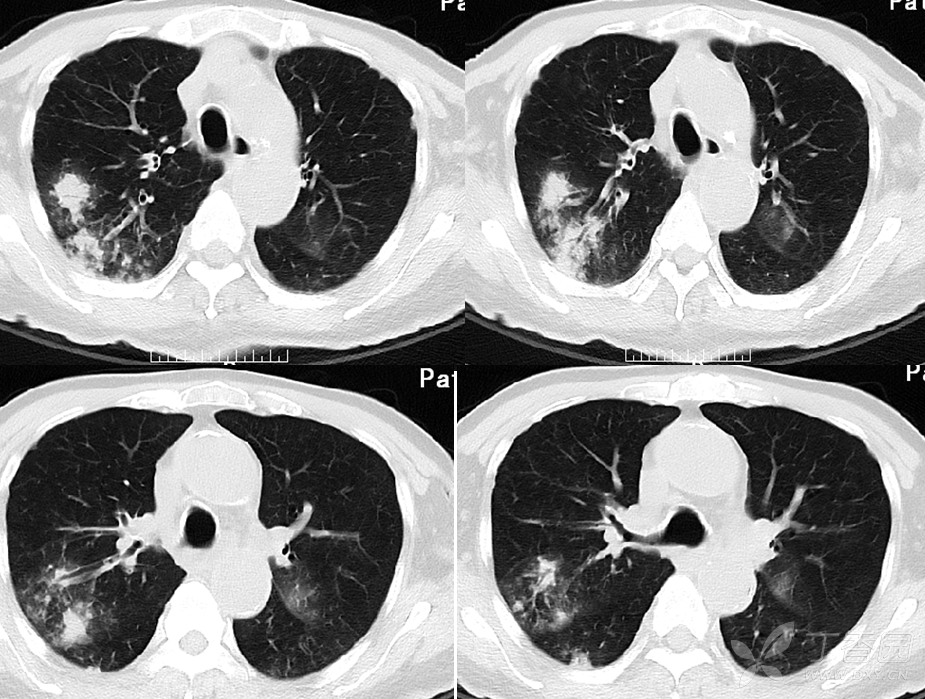

坠积性肺炎CT

但双下肺病灶明显增多,从ct表现并结合临床,双下肺为坠积性肺炎成立

35分胸部ct显示双肺下叶阴影,坠积性肺炎